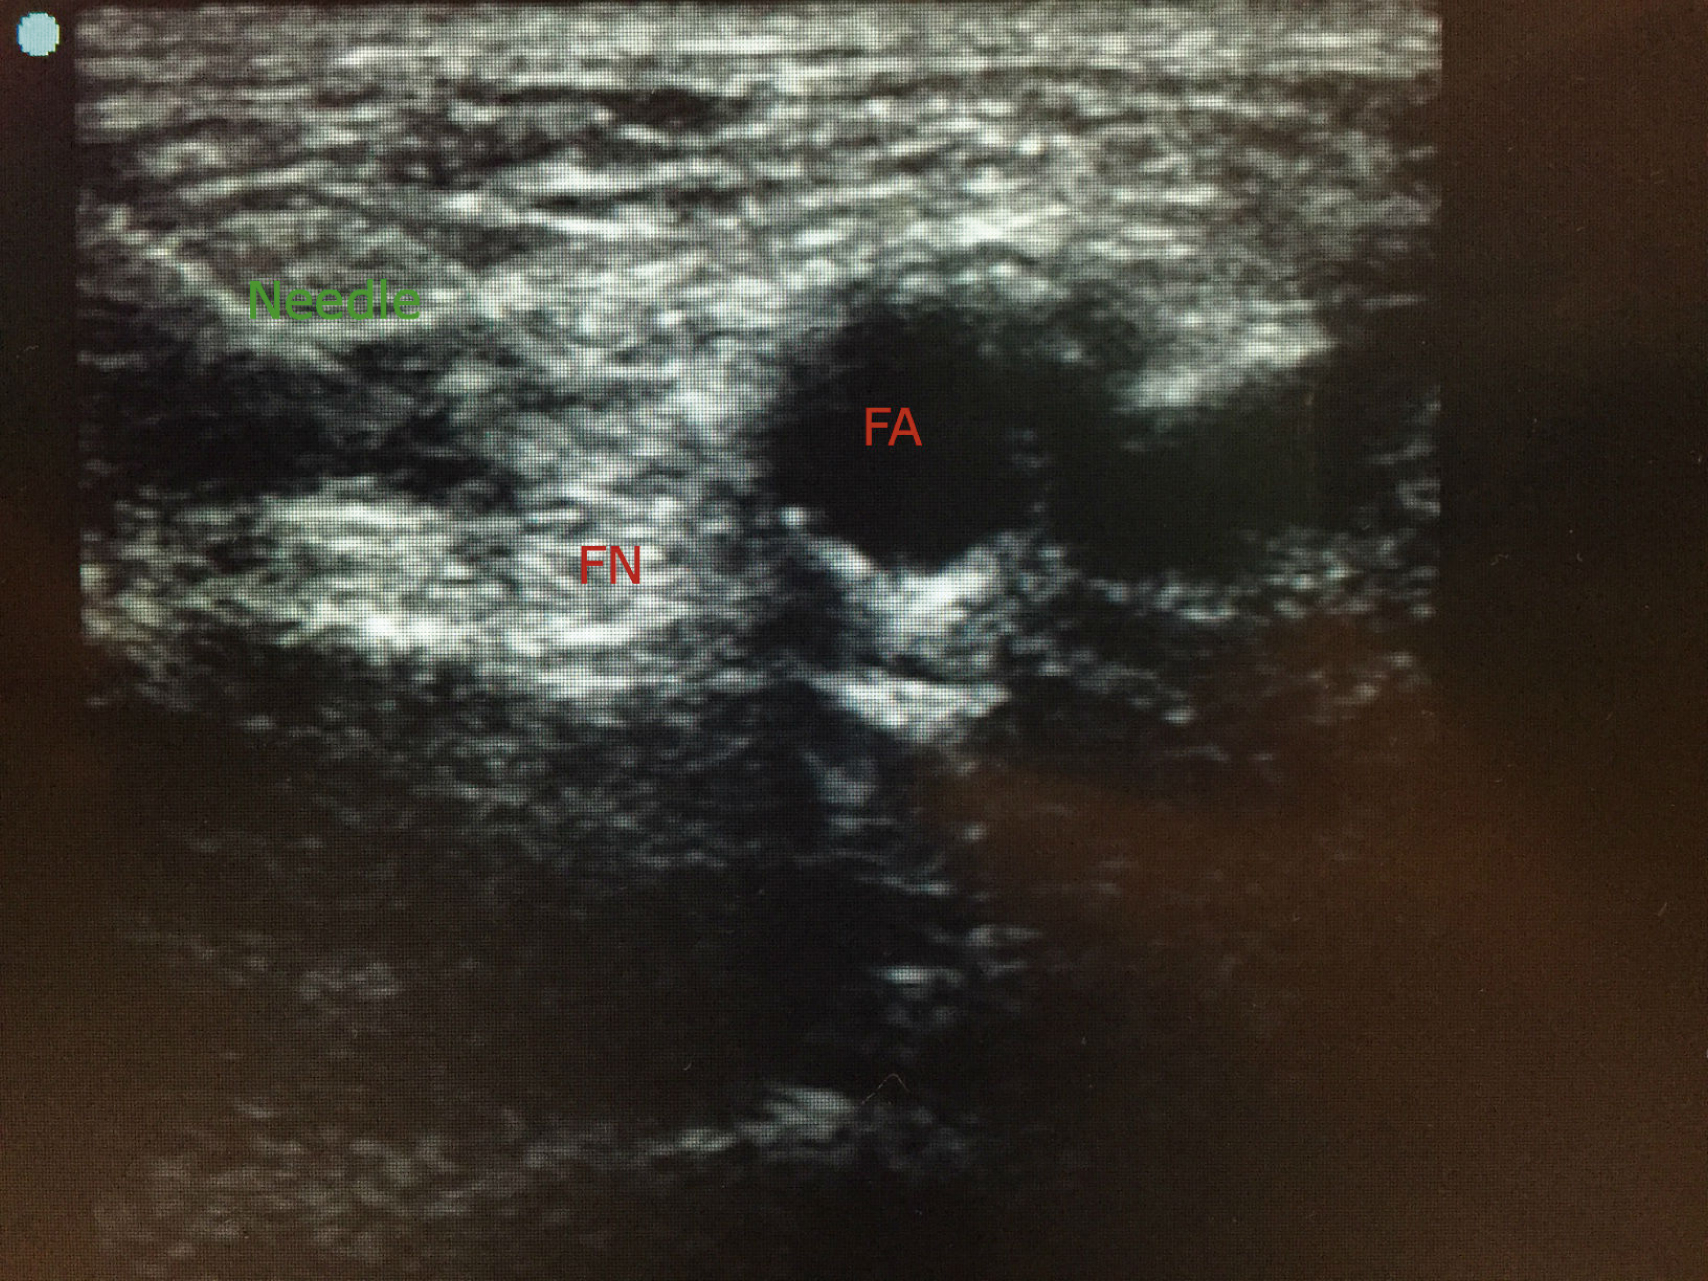

In our center, we utilize a combined approach under ultrasound guidance and nerve-stimulation (

Ultrasound and peripheral nerve stimulation-guided femoral nerve block injection over the left femoral nerve region showing the transducer position and needle insertion.

Ultrasound image showing the needle path (needle) to block the femoral nerve (FN). Blue dot marks the lateral side and femoral artery (FA) can be seen.